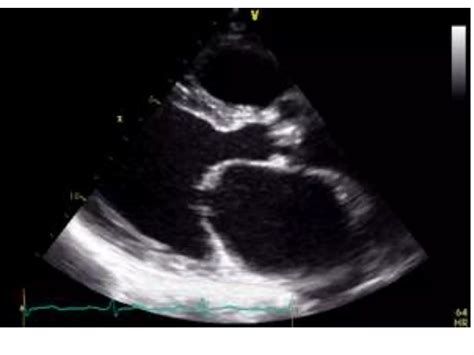

An echocardiogram, or *echo*, is a non-invasive diagnostic test that uses high-frequency sound waves to produce images of the heart. This procedure is invaluable in diagnosing and monitoring mitral stenosis. During a *mitral stenosis echo*, the ultrasound waves bounce off the heart's structures, creating detailed images that can be analyzed by a cardiologist.

• Transthoracic Echocardiogram (TTE): This is the most common type, where the ultrasound probe is placed on the chest to capture images of the heart.